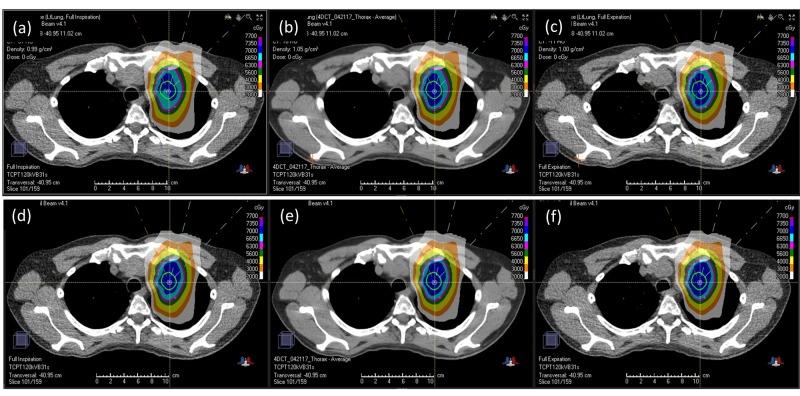

Purpose  This study aimed to evaluate the effectiveness of four-dimensional (4D) robust optimization for proton pencil-beam scanning (PBS) treatment of lung tumors. Patients and methods  In seven patients with lung cancer, proton beam therapy was planned using 4D robust optimization over 4D computed tomography (CT) data sets. The gross target volume (GTV) was contoured based on individual breathing phases, and a 5-mm expansion was used to generate the clinical target volume (CTV) for each phase. The 4D optimization was conducted directly on the 4D CT data set. The robust optimization settings included a CT Hounsfield unit (HU) uncertainty of 4% and a setup uncertainty of 5 mm to obtain the CTV. Additional target dose objectives such as those for the internal target volume (ITV) as well as the organ-at-risk (OAR) dose requirements were placed on the average CT. For comparison, three-dimensional (3D) robust optimization was also performed on the average CT. An additional verification 4D CT was performed to verify plan robustness against inter-fractional variations. Results  Target coverages were generally higher for 4D optimized plans. The difference was most pronounced for ITV V70Gy when evaluating individual breathing phases. The 4D optimized plans were shown to be able to maintain the ITV coverage at full prescription, while 3D optimized plans could not. More importantly, this difference in ITV V70Gy between the 4D and 3D optimized plans was also consistently observed when evaluating the verification 4D CT, indicating that the 4D optimized plans were more robust against inter-fractional variations. Less difference was seen between the 4D and 3D optimized plans in the lungs criteria: V5Gy and V20Gy. Conclusion  The proton PBS treatment plans optimized directly on the 4D CT were shown to be more robust when compared to those optimized on a regular 3D CT. Robust 4D optimization can improve the target coverage for the proton PBS lung treatments.

结果 4D优化计划的靶区覆盖通常更高。在评估个体呼吸相位时,差异在ITV V70Gy方面最为明显。结果显示4D优化计划能够在全处方剂量下维持ITV覆盖,而3D优化计划则不能。更重要的是,在评估验证4D CT时,4D和3D优化计划在ITV V70Gy方面的这种差异也始终存在,表明4D优化计划对分次间变化更具稳健性。4D和3D优化计划在肺的指标V5Gy和V20Gy方面差异较小。